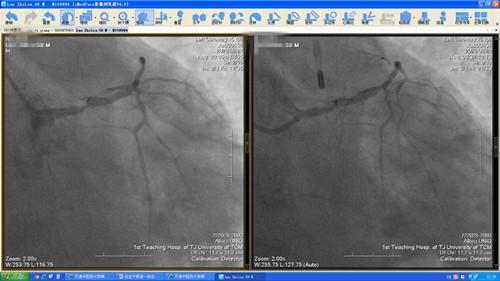

病例二,男性,55岁,因胸痛先后2次就诊于外院,建议口服药物或择期行冠脉造影检查,后患者因胸痛反复发作,就诊于华人策略心血管科门诊,患者安静休息时症状不典型,稍一活动就觉得胸痛,头晕,门诊接诊医师结合患者心电图及症状,考虑“急性冠脉综合征”,即刻联系心脏重症监护室联系住院,入院时已是周六中午,胸痛中心介入团队人员纷纷赶回医院投入手术,急诊冠脉造影显示左主干起始95%狭窄,无创通气辅助呼吸,置入IABP,无创呼吸机辅助通气,经过心血管科团队及导管室人员通力合作、密切配合,于左主干植入支架1枚,术后患者生命体征平稳,立即拔除IABP,撤除呼吸机,安返心脏重症监护室病房。

图2.2  第二例左主干病变造影及支架后造影结果